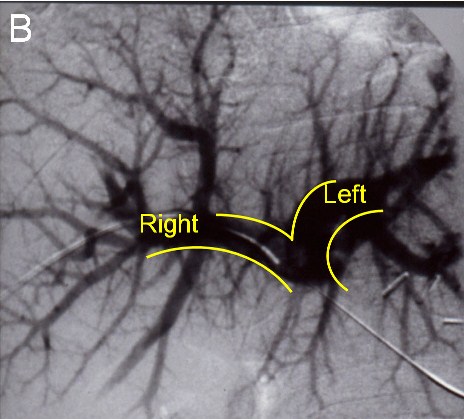

| (B) Before the next operation, a portal vein embolization is done: Venogram showing a normal portal vein prior to embolization |